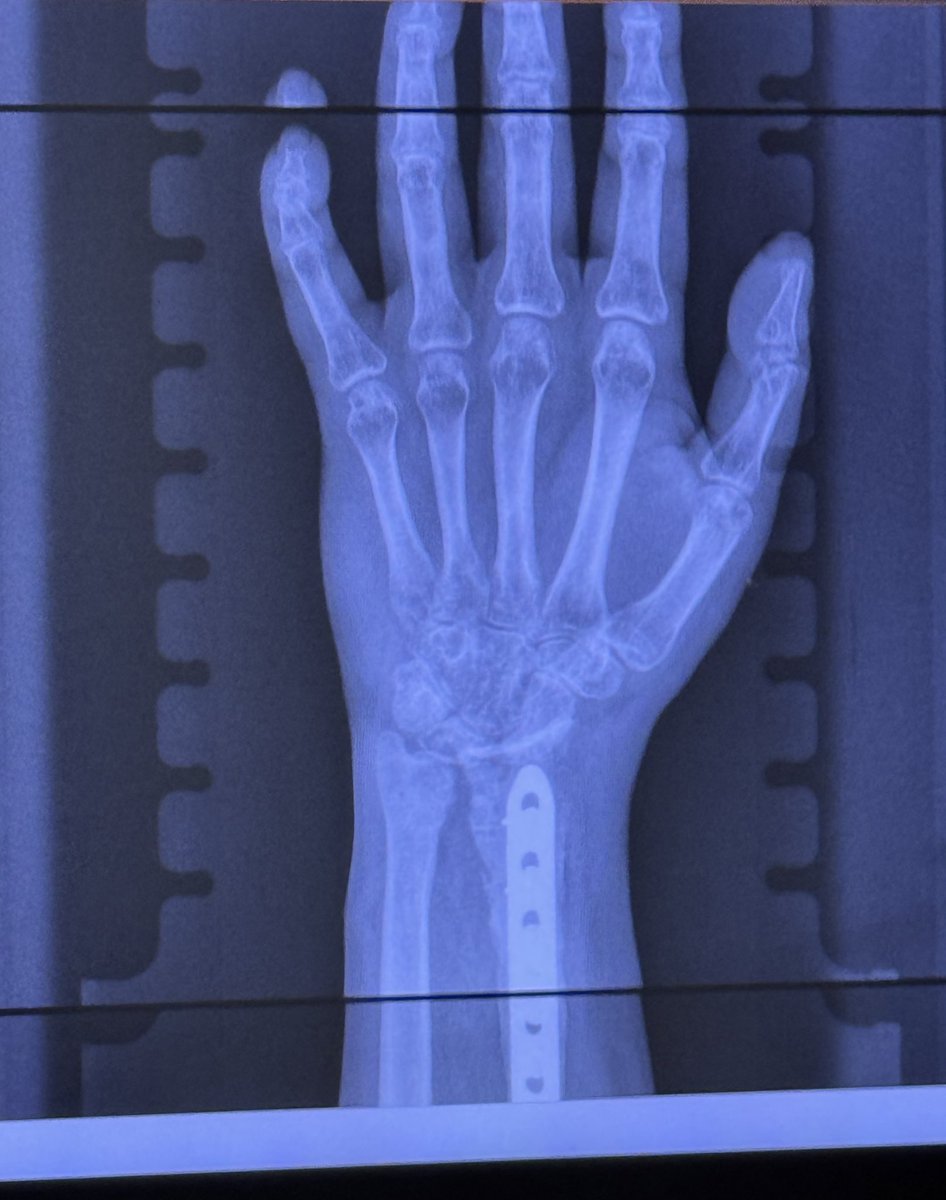

Bro as someone who went through something similar, two 6 inch plates, 14 screws, and a piece of my elbow to fix it, then all the hardware out 6 months later and a full bone graft.

Went to 5 different doctors before finding Alhidad Ghiassi. He’s now a private practice hand and arm specialist, but one of the best, he’s in LA, highly recommend